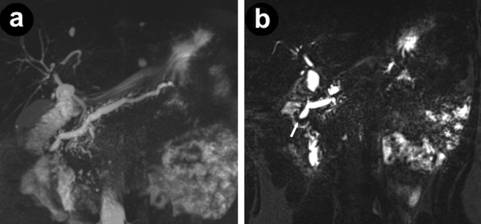

A fifty-year-old female with NF1 presented with several months of persistent non-specific abdominal pain. She had no significant past medical history and her symptoms and laboratory tests failed to identify a specific cause for her pain. Contrast enhanced computed tomography (CT) imaging showed a prominent pancreatic duct and a prominent minor duodenal papilla, without a pancreatic mass. Magnetic resonance cholangiopancreatography further confirmed a grossly dilated pancreatic duct, pancreas divisum, and a suggestion of a mass at the level of the minor papilla (Figure 1). Endoscopic ultrasound (EUS) confirmed a 1.7 cm tumor confined to the minor papilla. Fine needle aspiration biopsy was non-diagnostic. Endoscopic retrograde pancreatography further confirmed an obstructing mass, but biopsy results were inconclusive. Repeat endoscopic retrograde pancreatography was undertaken, with further biopsies, but the results were once again non-diagnostic. Mild pancreatitis requiring hospitalization occurred following biopsy attempts. She underwent further imaging in the form of 18fluorine-fluoro-2-deoxyglucose positron emission tomography/computed tomography (18F-FDG-PET/CT and 68gallium (Ga) DOTATATE PET, both of which were negative. Blood tests including chromogranin A were normal.

Figure 1. Magnetic resonance imaging showing a diffusely dilated pancreatic duct (a.) from the level of the minor papilla with the finding of pancreatic divisum. (b.) Impression of a mass (arrow) at the minor papilla can be seen. |